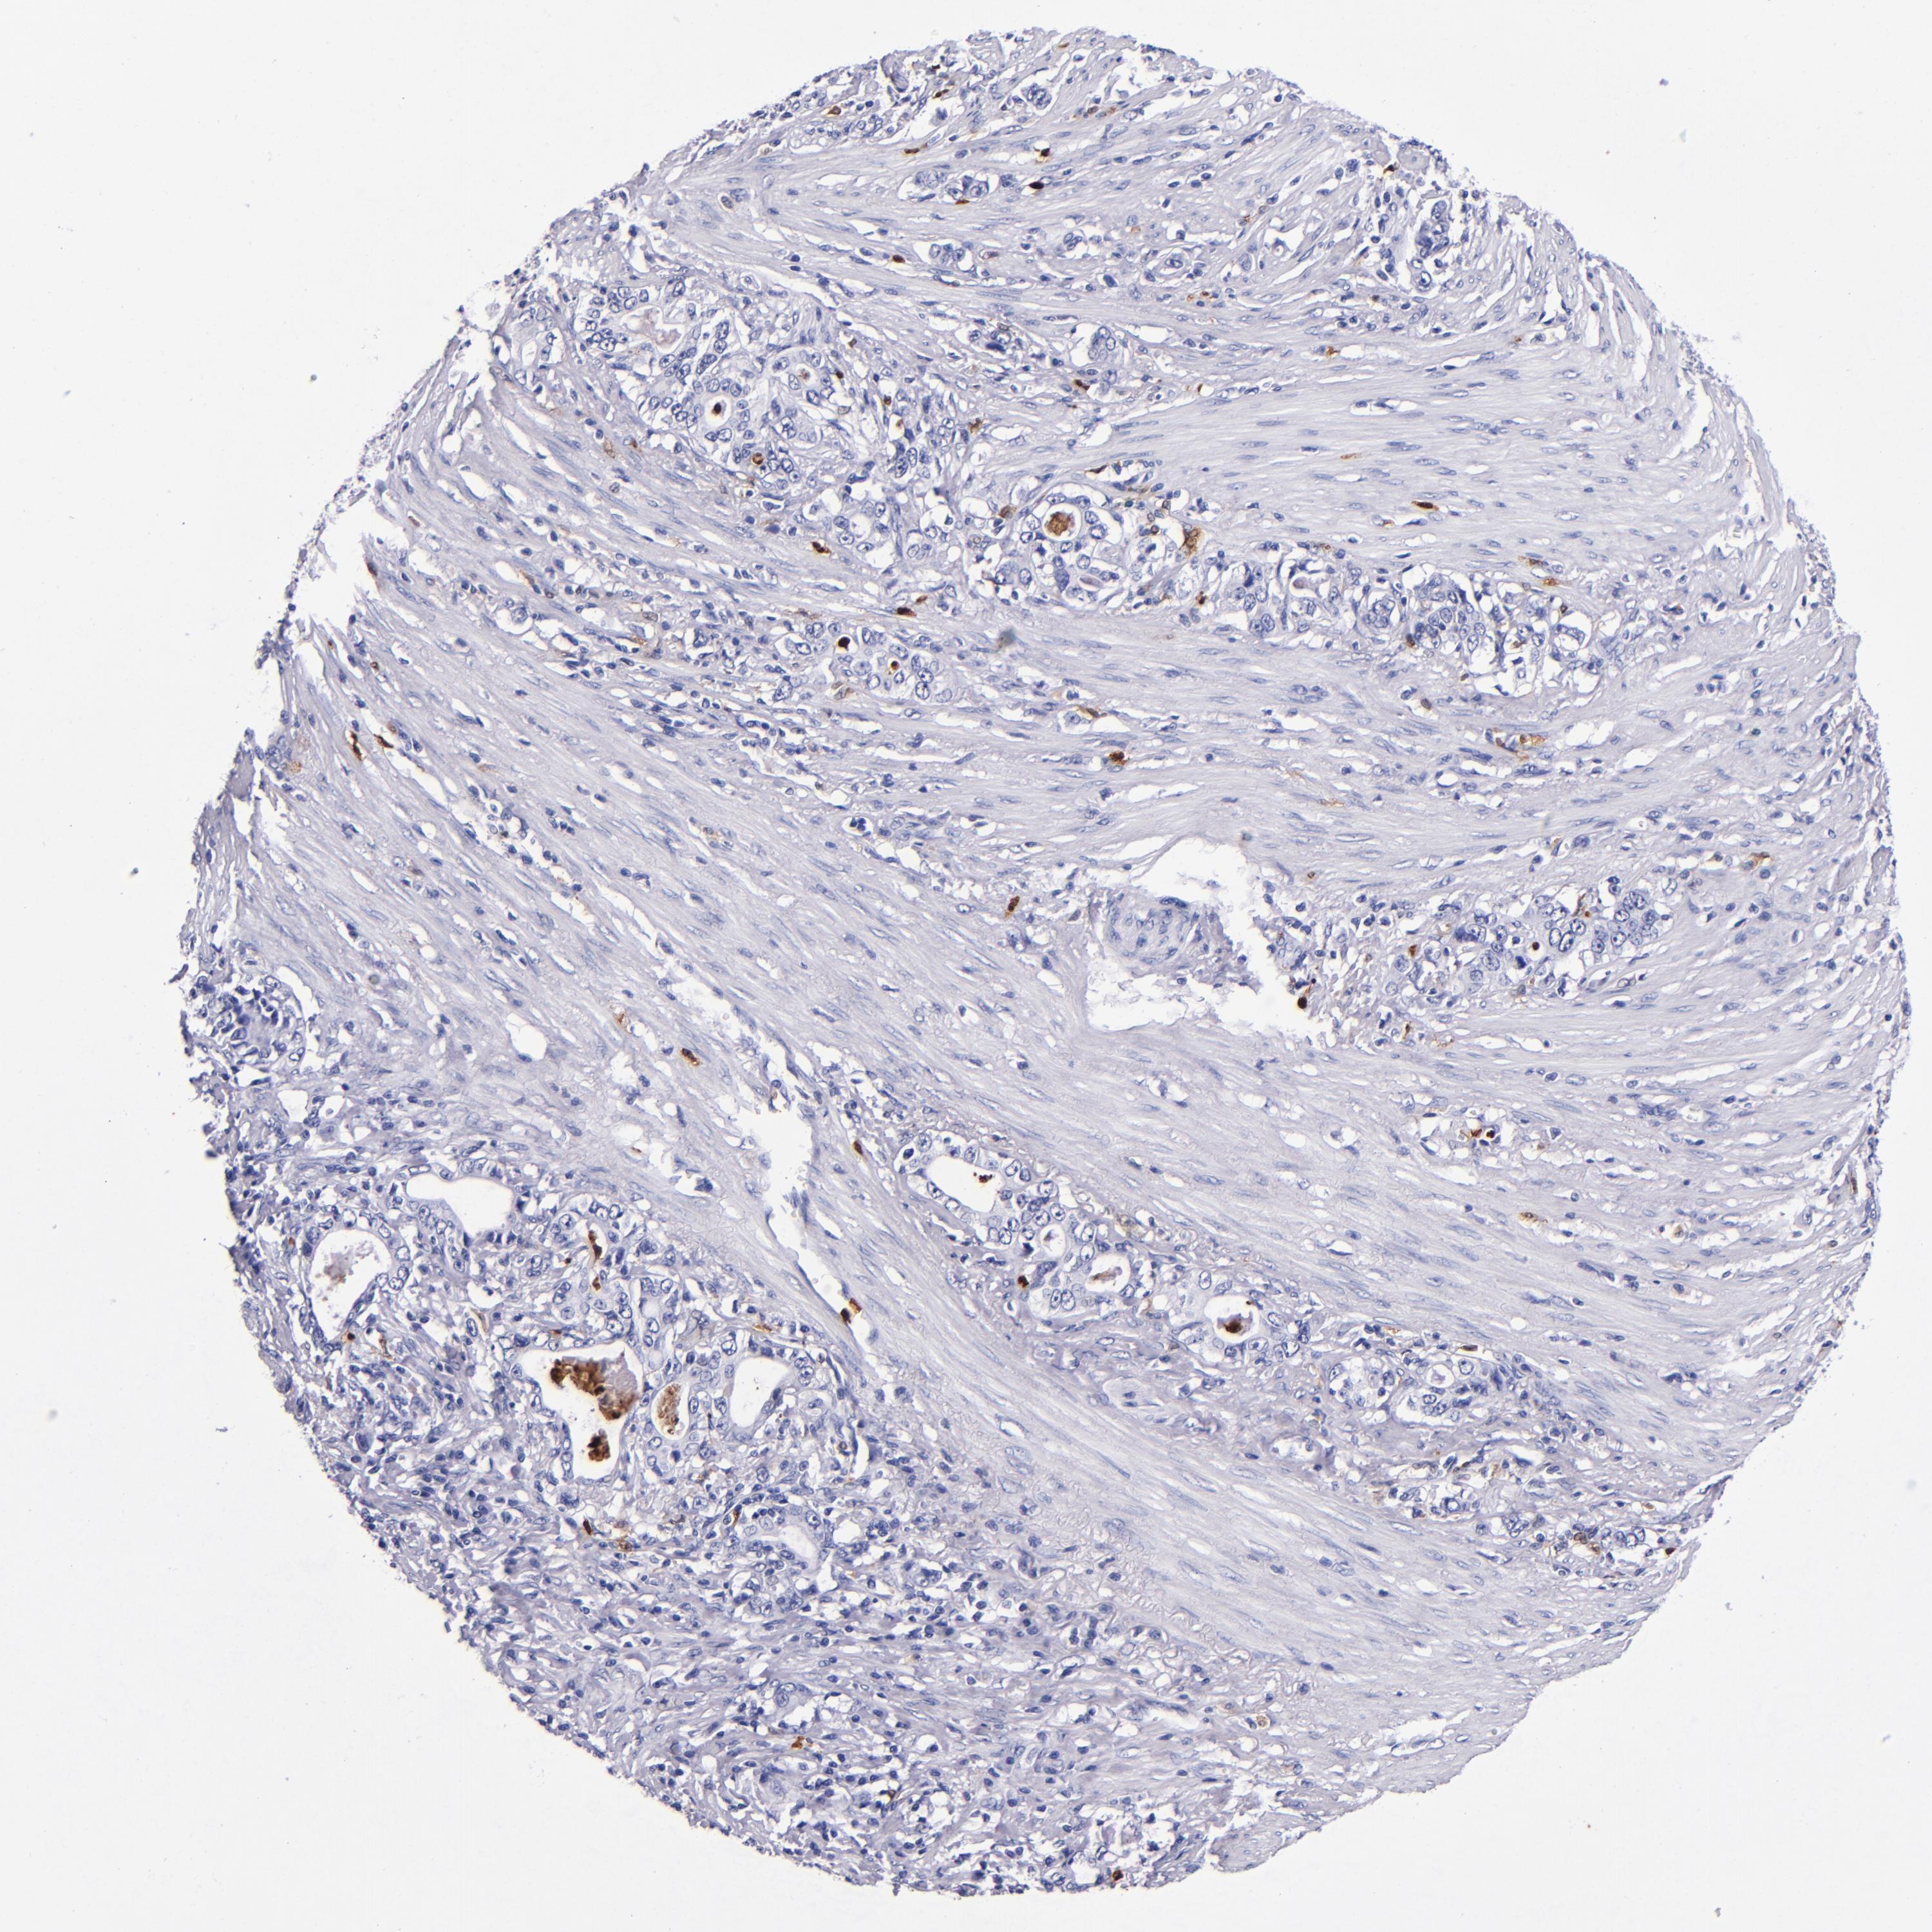

STOMACH CANCER - Protein expressioni

A mouse-over function shows sample information and annotation data. Click on an image to view it in a full screen mode. Samples can be filtered based on level of antibody staining by selecting one or several of the following categories: high, medium, low and not detected. The assay and annotation is described here.

Note that samples used for immunohistochemistry by the Human Protein Atlas do not correspond to samples in the TCGA dataset.

Antibody stainingi

Antibody staining in the annotated cell types in the current human tissue is reported as not detected, low, medium, or high, based on conventional immunohistochemistry profiling in selected tissues. This score is based on the combination of the staining intensity and fraction of stained cells.

Each image is clickable and will lead to virtual microscopy that enables deeper exploration of all samples and also displays staining intensity scores, fraction scores and subcellular localization as well as patient and tissue information for each sample.

Antibody HPA024372

Antibody CAB002791

Staining

High

Medium

Low

Not detected

Adenocarcinoma, NOS

Adenocarcinoma, High grade